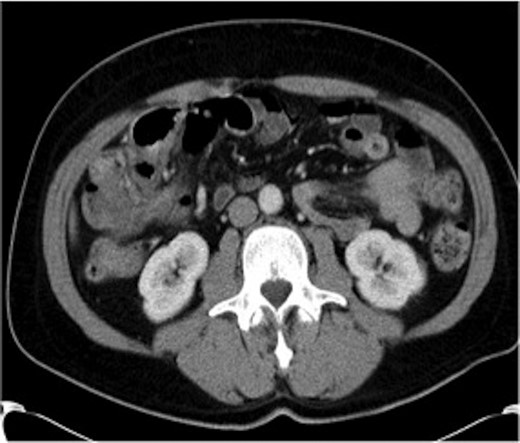

A gastrografin enema (Fig. 4) failed to demonstrate any flow beyond the mid-transverse colon. A presumptive diagnosis of transverse colon obstruction was made and the patient was taken to theatre.

Gastrografin enema (Case 2) demonstrating no flow beyond the mid-transverse colon.